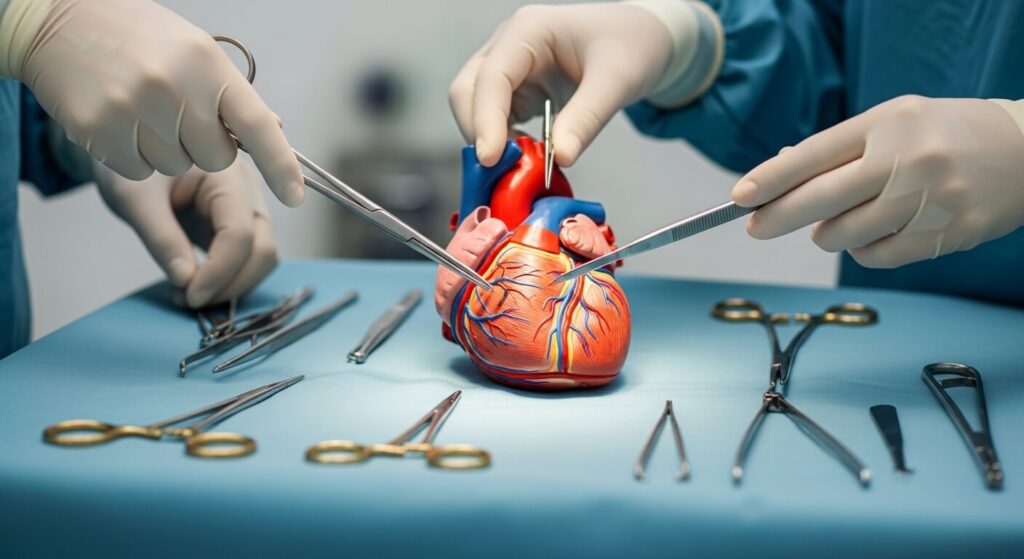

Essential Instruments Used in Cardiovascular Surgery

Basic Surgical Instruments

Basic surgical instruments include scissors, forceps, clamps, and needle holders. These are standard tools used in many types of surgeries. However, in cardiac procedures, they are often designed with extra precision for delicate work.

Specialized Cardiac Tools

Specialized cardiac tools are used to handle blood vessels and heart tissues carefully. Some instruments help keep vessels open, while others control bleeding. There are also machines that temporarily assist with blood circulation during certain procedures.

Understanding Equipment Without Complex Terminology

Understanding equipment without relying on complex terminology is important. Focus on function rather than name. Ask yourself: What does this tool do? Why is it used at this step?

As you gain experience, these instruments will become familiar. They won’t feel intimidating — they’ll feel like extensions of your role.

Mastering instrument knowledge builds confidence. And in cardiovascular surgery, confidence supports performance.